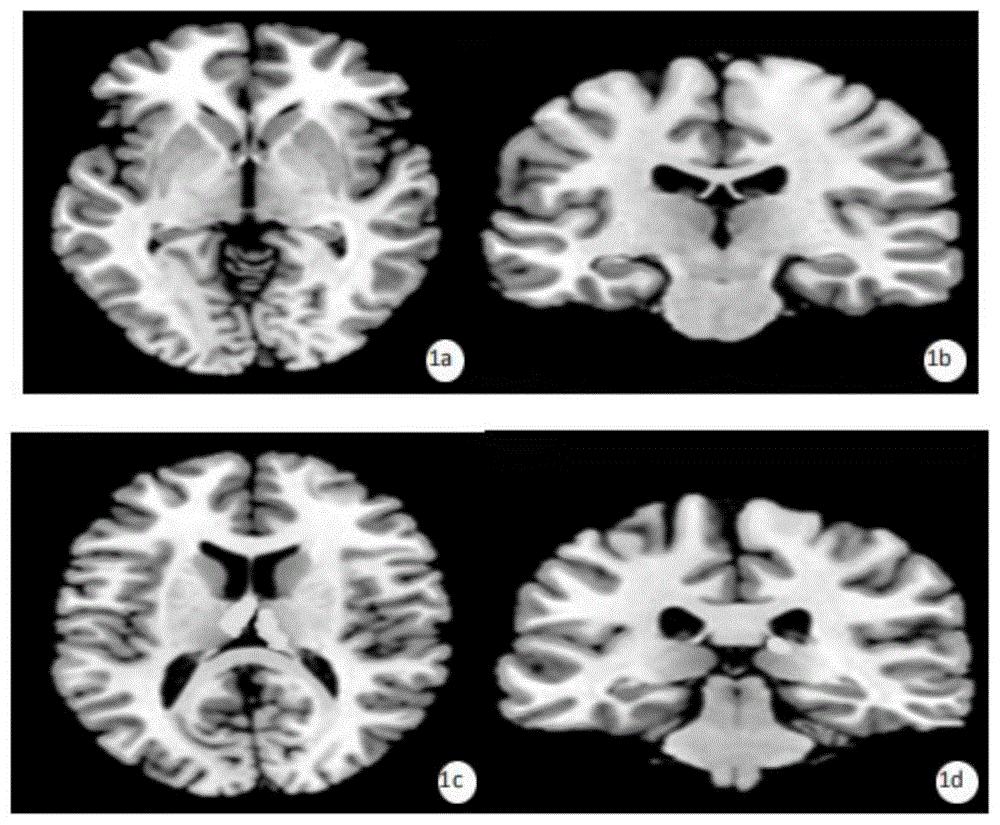

1、脑CT或脑磁共振成像(MRI)检查

核磁共振显示病变下的弓状纤维开始侵犯双半球的深部白质,表现为弥漫性的长T2信号,可侵犯基底神经节,并可侵犯小脑、脑干和脊髓。脑部 CT显示异常,如脑水肿。

从临床表现来看,头颅 MRI发展缓慢,头围过大,初期肌张力下降,皮质硬度下降,视神经萎缩,痉挛发作,颅内 MRI呈弥漫性变化,上皮纤维母细胞文化发现,天冬氨酰转移酶活性下降,脑脊液正常,脑电图不明确。